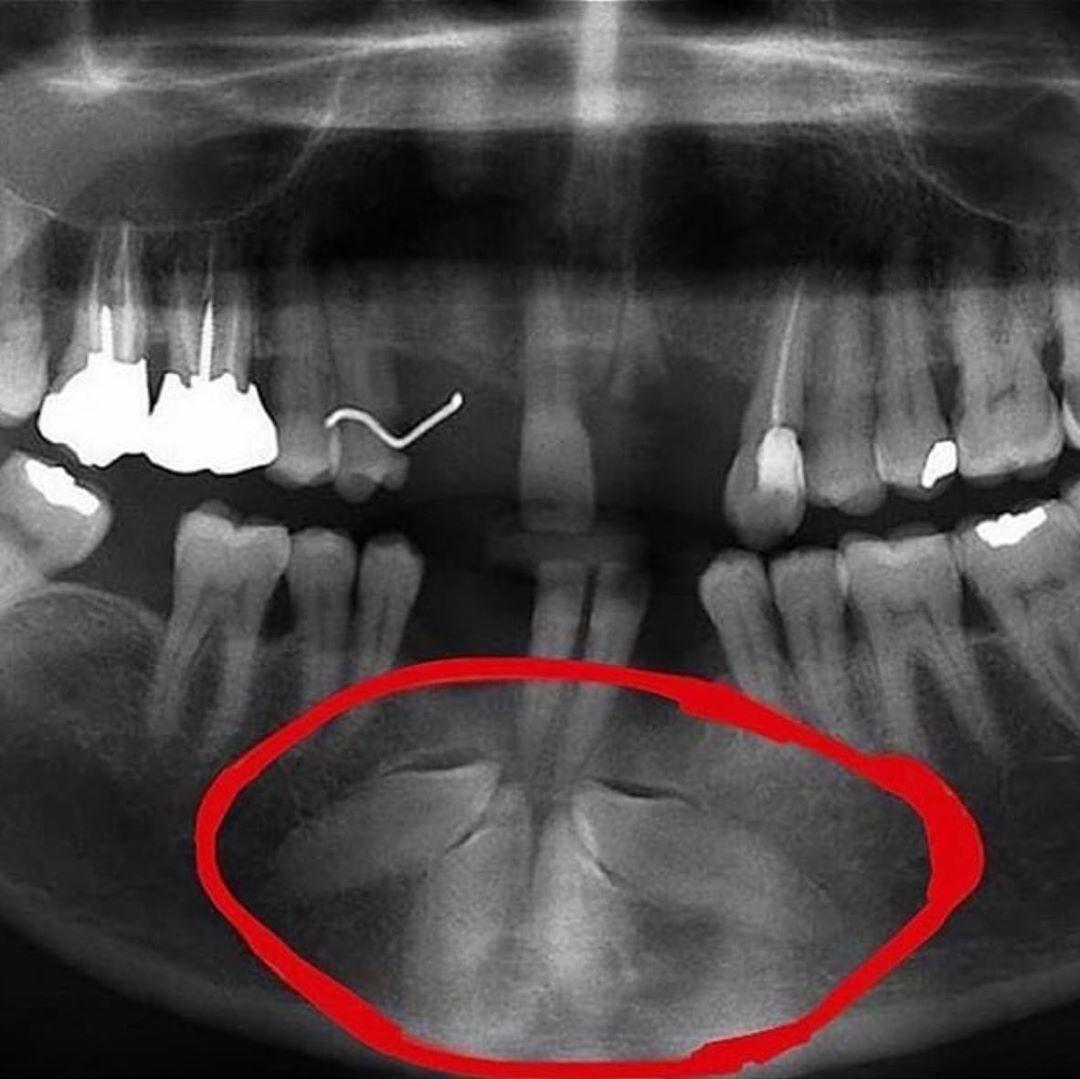

Одонтома нижней челюсти: фотографии и медицинская информация